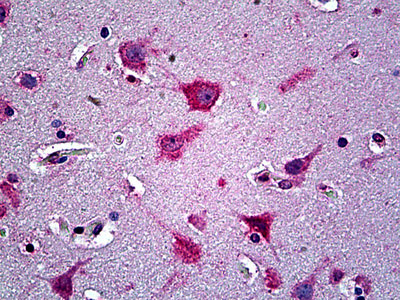

Anti-EFNA5 / Ephrin A5 antibody IHC of human brain, cortex.